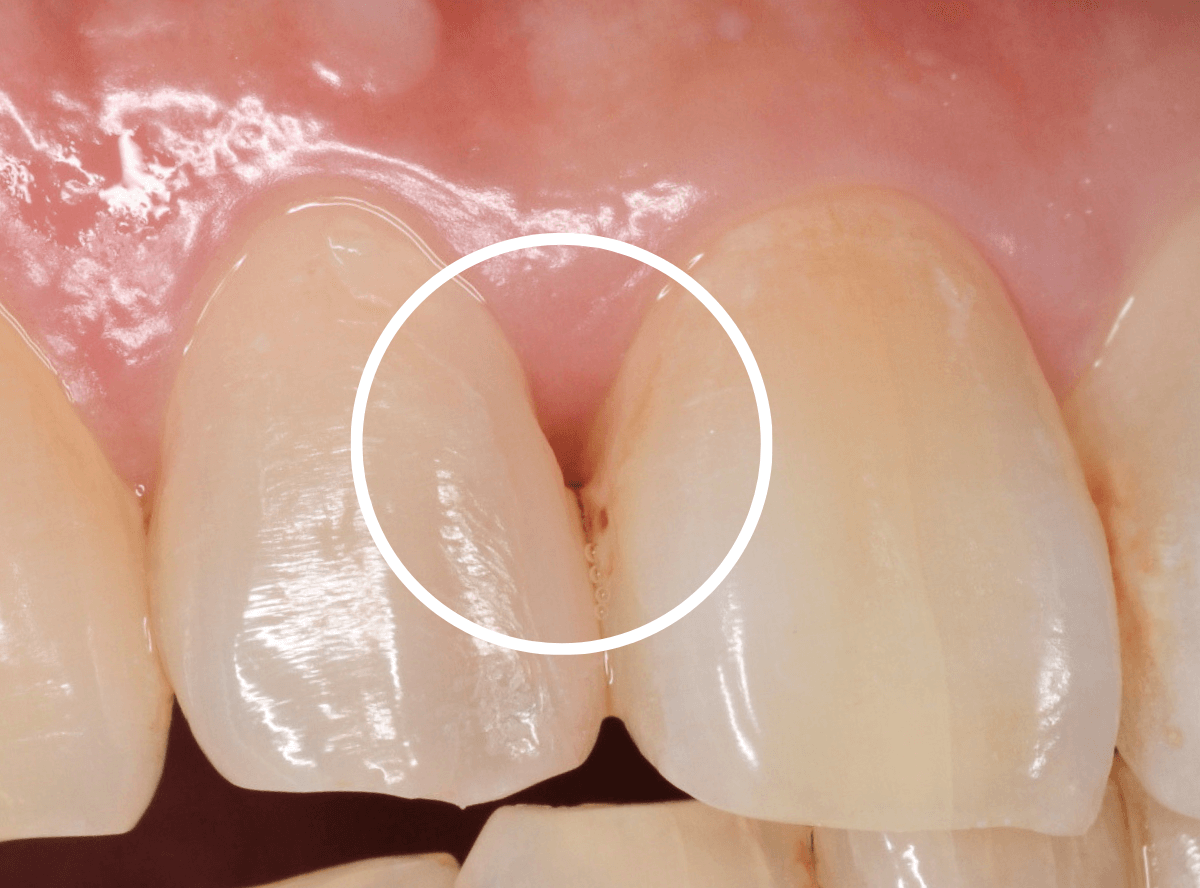

そして、後ろの歯との境の〇部には汚れや歯石が多くつまっています。

虫歯と共に、歯の周りの縁下歯石除去も行いました。

歯の周りがきれいになっているのがわかると思います。